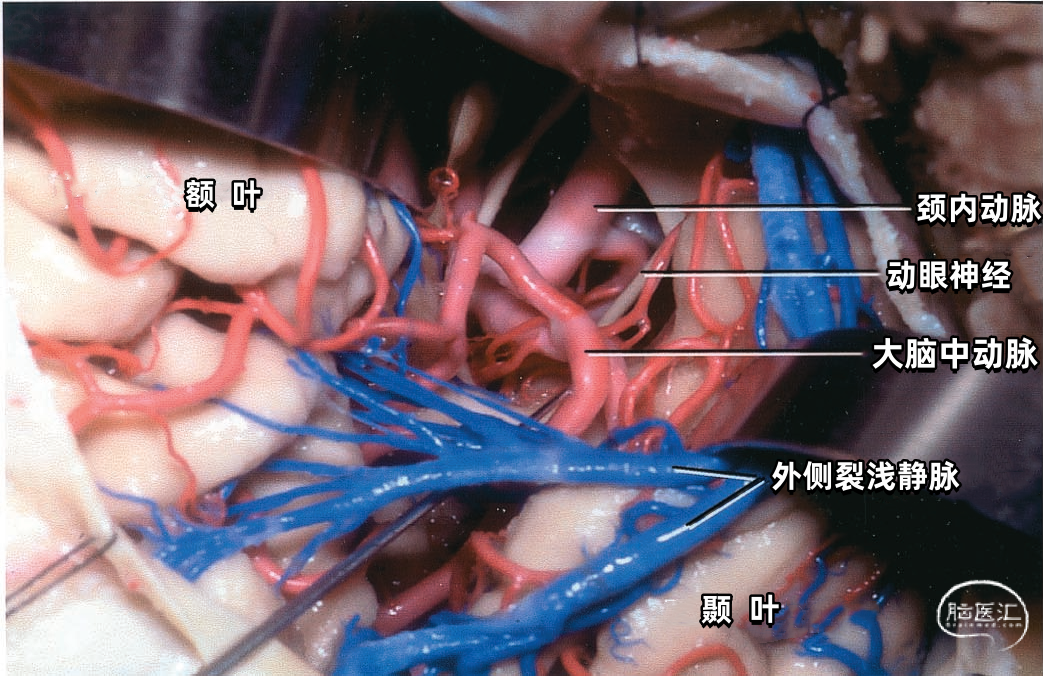

▼3.外侧裂浅静脉

外侧裂浅静脉通常起自外侧裂后端,沿外侧裂唇行向前下。它可能以两支起始,但通常在沿蝶骨嵴进入静脉窦之前融合为一支。 外侧裂浅静脉接受额外侧裂静脉、顶外侧裂静脉和颞外侧裂静脉的回流,并经常与Trolard静脉和Labbé静脉相吻合。它穿经覆盖外侧裂前端的蛛网膜,在蝶骨嵴内侧部下方加入蝶顶窦,或直接进入海绵窦。它也有可能离开外侧裂,围绕颞极,进入中颅窝底的硬膜窦,引流入岩上窦,或通过蝶骨的小孔出颅与翼静脉丛相交通。 如果外侧裂浅静脉细小或缺如,则相邻的静脉将代替引流其区域。起自外侧裂上唇的静脉,向上引流加入进入上矢状窦的静脉;起自外侧裂下唇的静脉,直接向后下,汇入颞叶下方的硬膜窦。如果外侧裂浅静脉的中部缺如,则静脉前部加入蝶骨嵴的硬膜窦,而后部则加入Trolard和Labbé吻合静脉。

下图示打开外侧裂,牵拉外侧裂浅静脉显露颈内动脉和大脑中动脉。